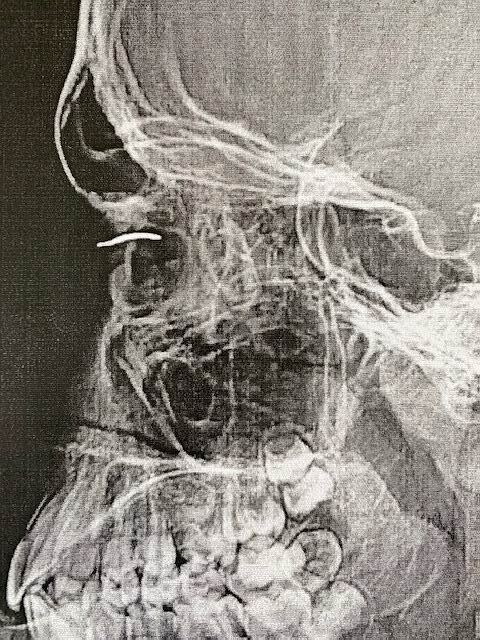

Дитина отримала проникаюче поранення ока, в ньому застряг уламок дроту від батога.

Як зазначають у лікарні, вдома робили невдалу спробу самостійно витягнути дріт.

Після того, як хлопчика прооперували, зір відновився до 100%.